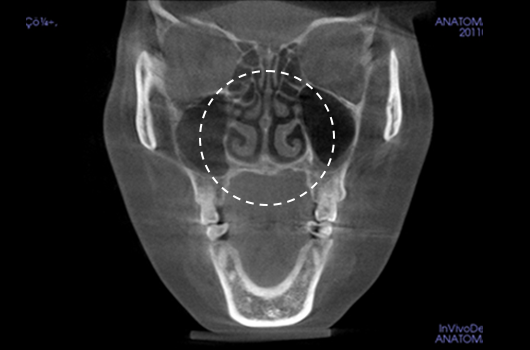

4. Diagnosis of inferior turbinate asymmetry and surgery for nasal obstruction

Diagnosis of inferior turbinate asymmetry and surgery for nasal obstruction